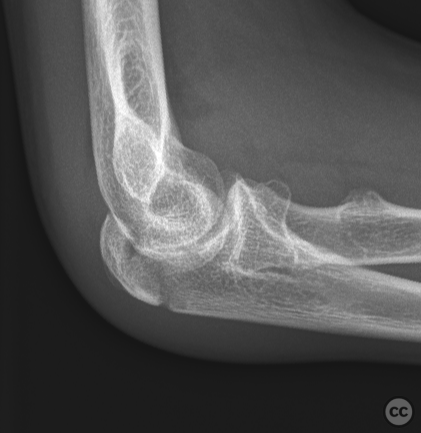

Endobutton fixation of an O’Driscoll ant...

Brussels, Belgium

Ulna - AO/OTA 2Ux